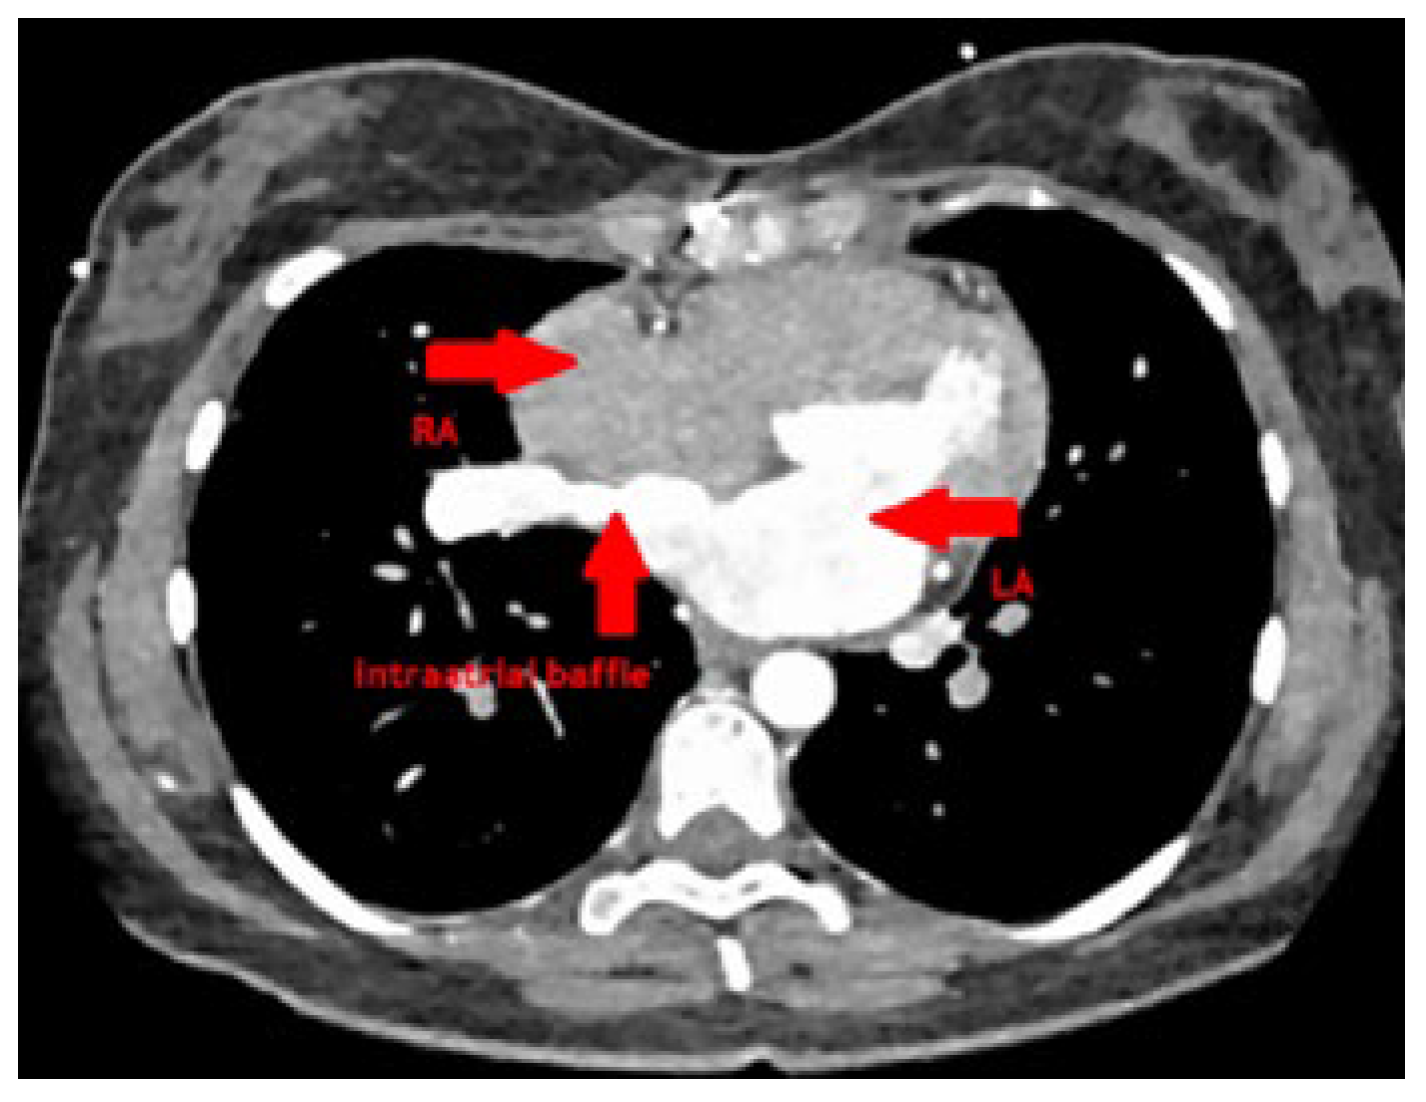

At follow-up after 3 months, she was well recovered and reported marked improvement of her exercise capacity as well as her dyspnoea. CT scan showed a good postoperative result without any stenosis of the redirected pulmonary vein and a wide baffie tunnel into the left atrium (Figure 5). Transthoracic echocardiography 5 months after surgery showed unobstructed flow across the redirected right pulmonary vein and the baffie and normalised right ventricle dimensions and function.

Figure 5. The postoperative, corrected situs with the redirected right pulmonary vein into the left atrium via intra-atrial baffle (arrow). LA (arrow): left atrium; RA (arrow): right atrium.